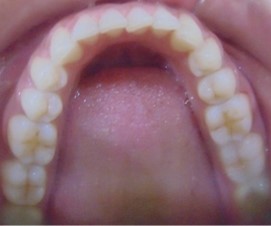

Divya Patil, 28Y, Duration - 6Months

Before

After

Image 1